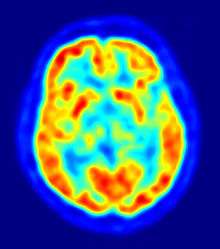

Although the human brain represents only 2% of the body weight, it receives 15% of the cardiac output, 20% of total body oxygen consumption, and 25% of total body glucose utilization.[34] The need to limit body weight has led to selection for a reduction of brain size in some species, such as bats, who need to be able to fly.[35] The brain mostly uses glucose for energy, and deprivation of glucose, as can happen in hypoglycemia, can result in loss of consciousness. The energy consumption of the brain does not vary greatly over time, but active regions of the cortex consume somewhat more energy than inactive regions: this fact forms the basis for the functional brain imaging methods PET and fMRI.[36] These are nuclear medicine, functional imaging techniques which produce a three-dimensional image of metabolic activity.

Structural and functional imaging

There are several methods for detecting brain activity changes using three-dimensional imaging of local changes in blood flow. The older methods are SPECT and PET, which depend on injection of radioactive tracers into the bloodstream. A newer method, functional magnetic resonance imaging (fMRI), has considerably better spatial resolution and involves no radioactivity.[46] Using the most powerful magnets currently available, fMRI can localize brain activity changes to regions as small as one cubic millimeter. The downside is that the temporal resolution is poor: when brain activity increases, the blood flow response is delayed by 1–5 seconds and lasts for at least 10 seconds. Thus, fMRI is a very useful tool for learning which brain regions are involved in a given behavior, but gives little information about the temporal dynamics of their responses. A major advantage for fMRI is that, because it is non-invasive, it can readily be used on human subjects. Another new non-invasive functional imaging method is functional near-infrared spectroscopy.